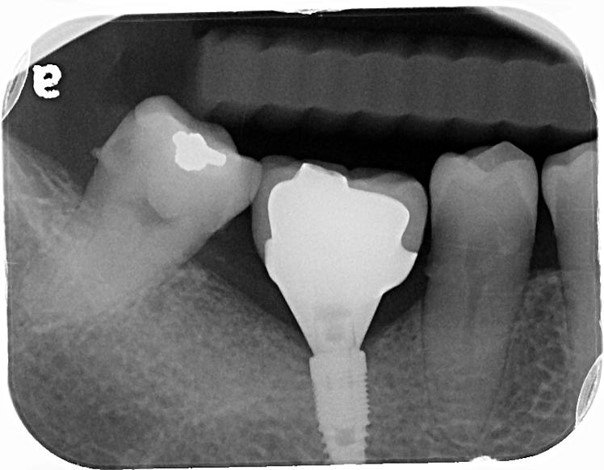

治療前,右下第三大臼齒冷熱敏感

治療前,蛀牙已侵犯至牙髓

顯微根管治療

鑄造金屬釘柱

水雷射牙冠增長手術